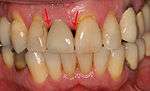

Bone loss (peri-implantitis) on implants over 7 years in a heavy smoker

Black triangles caused by bone loss between implants and natural teeth